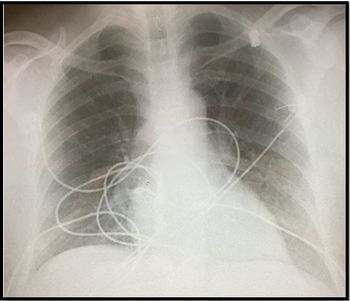

A 19-year-old previously healthy man presents with intermittent diarrhea, fever, and weight loss with pleuritic left-sided chest pain for 1 month. What does the chest x-ray show?